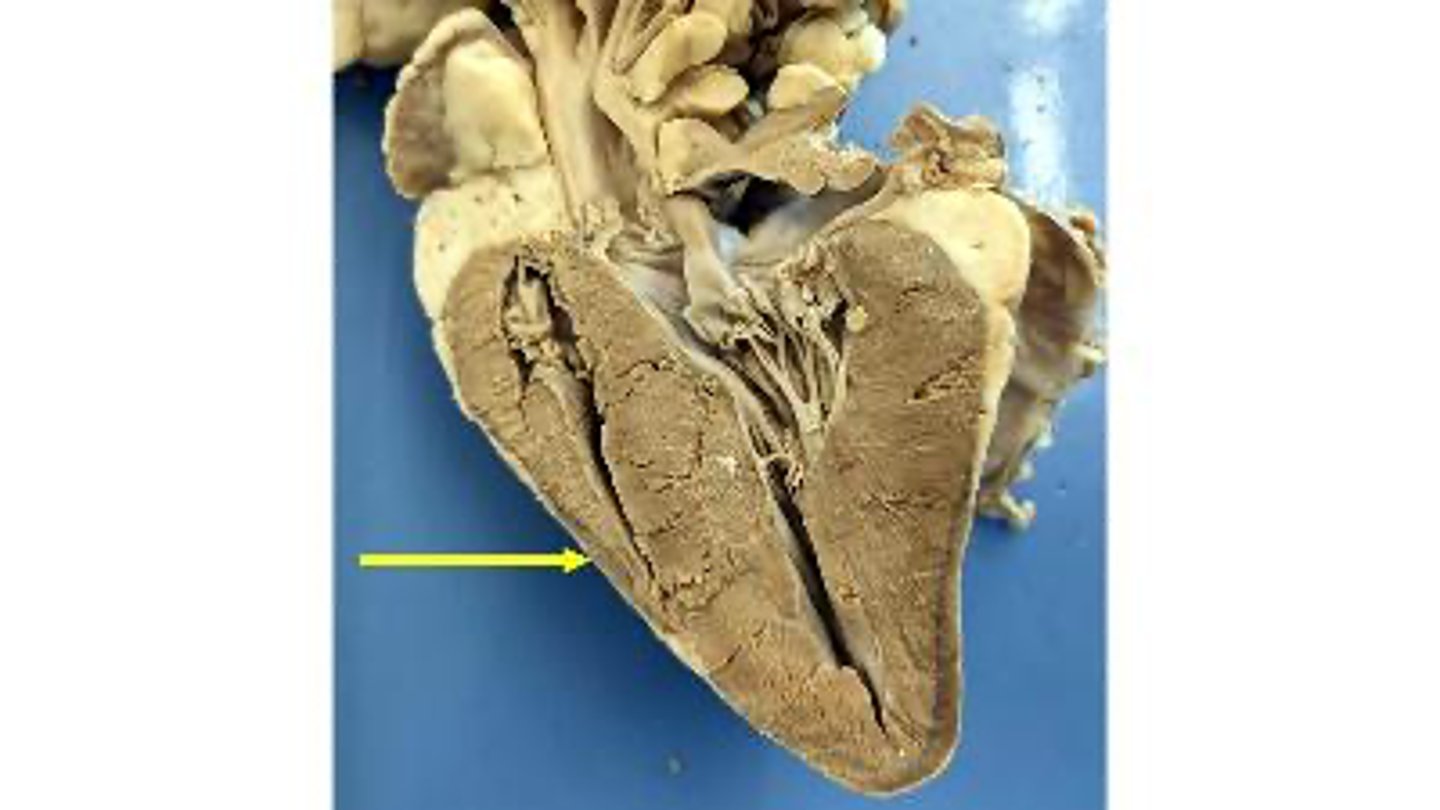

aortic valve

Name the membranous structure

right auricle

Name the ear-like structure

apex

Name the region of the organ

left ventricle

Name the chamber

interventricular septum

Name the dividing wall indicated

chordae tendineae

Name the structures

right ventricle

endocardium

Name the membrane

epicardium

Name the layer

myocardium